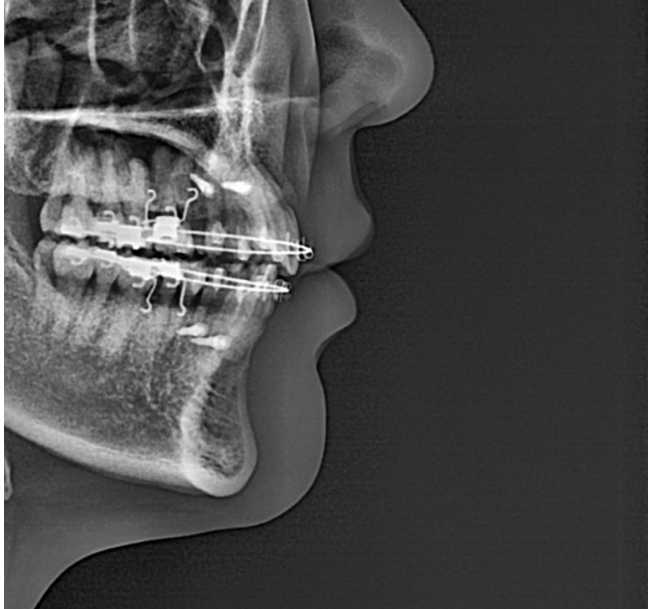

25.04

치근흡수는 없으며 치근평행도는 좋습니다.